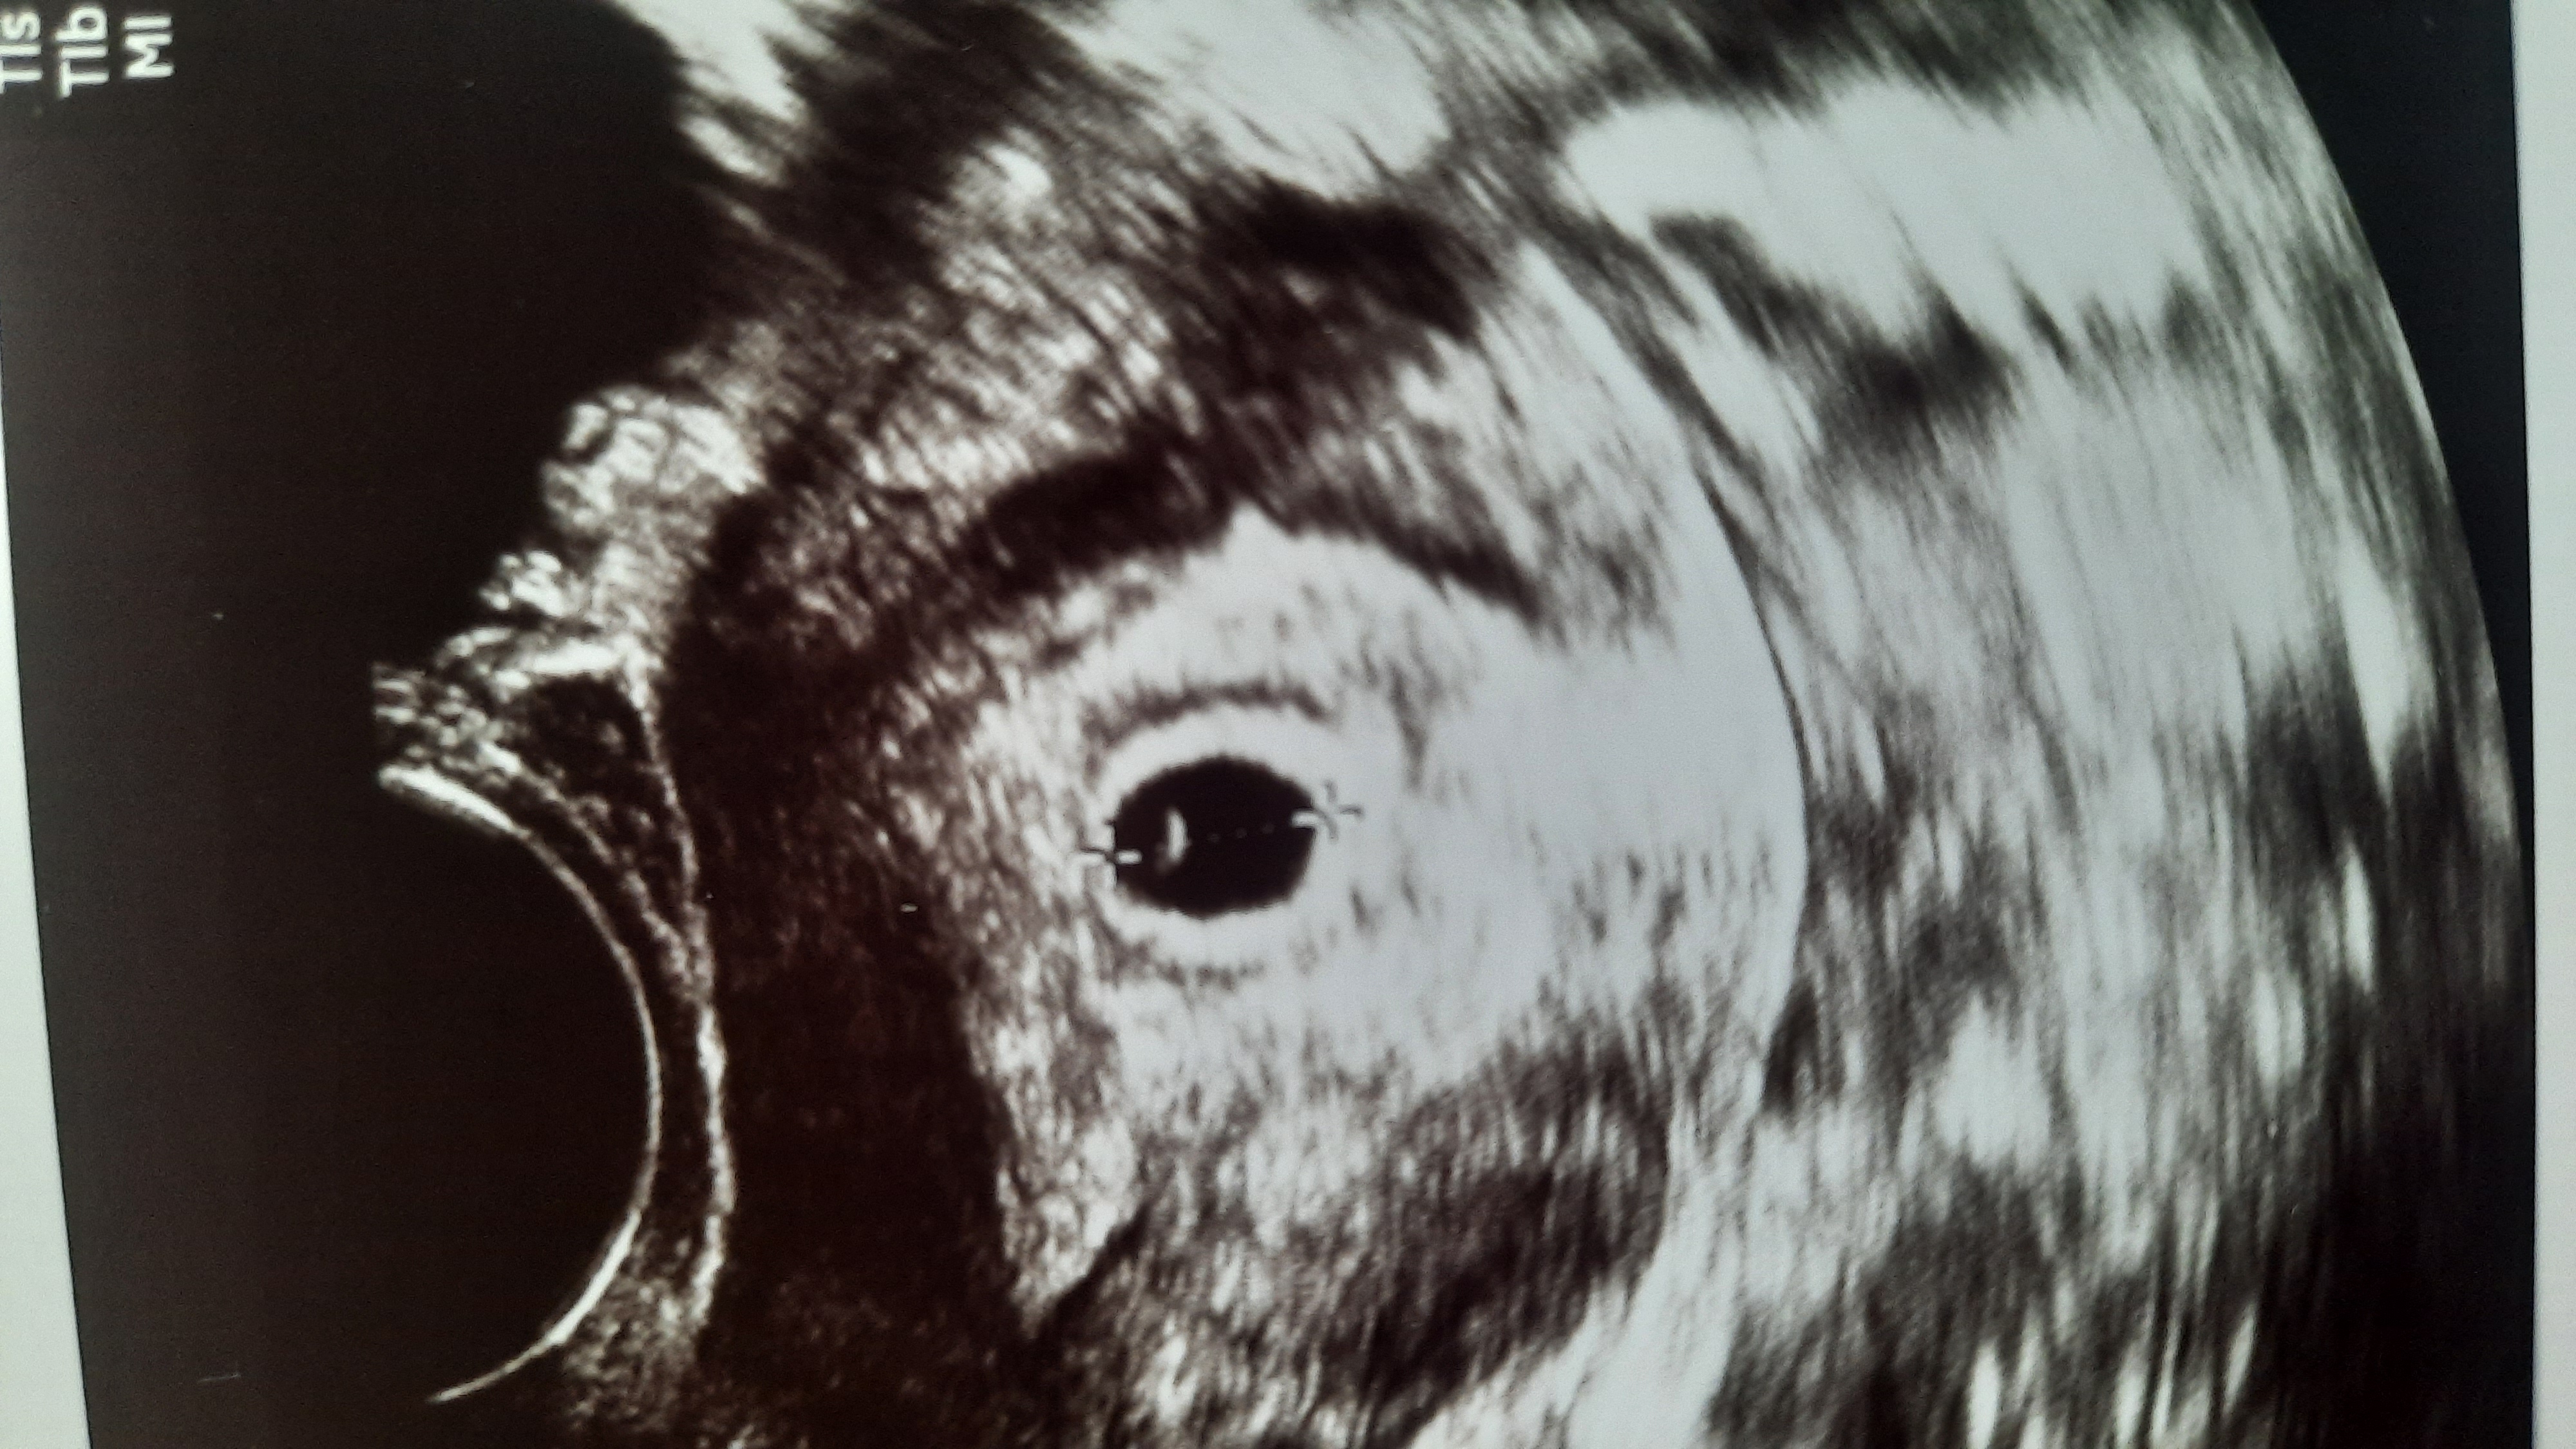

Ирина , а вот 5 недель Изображение

Ирина , я думаю мальчик по этому УЗИ :)))